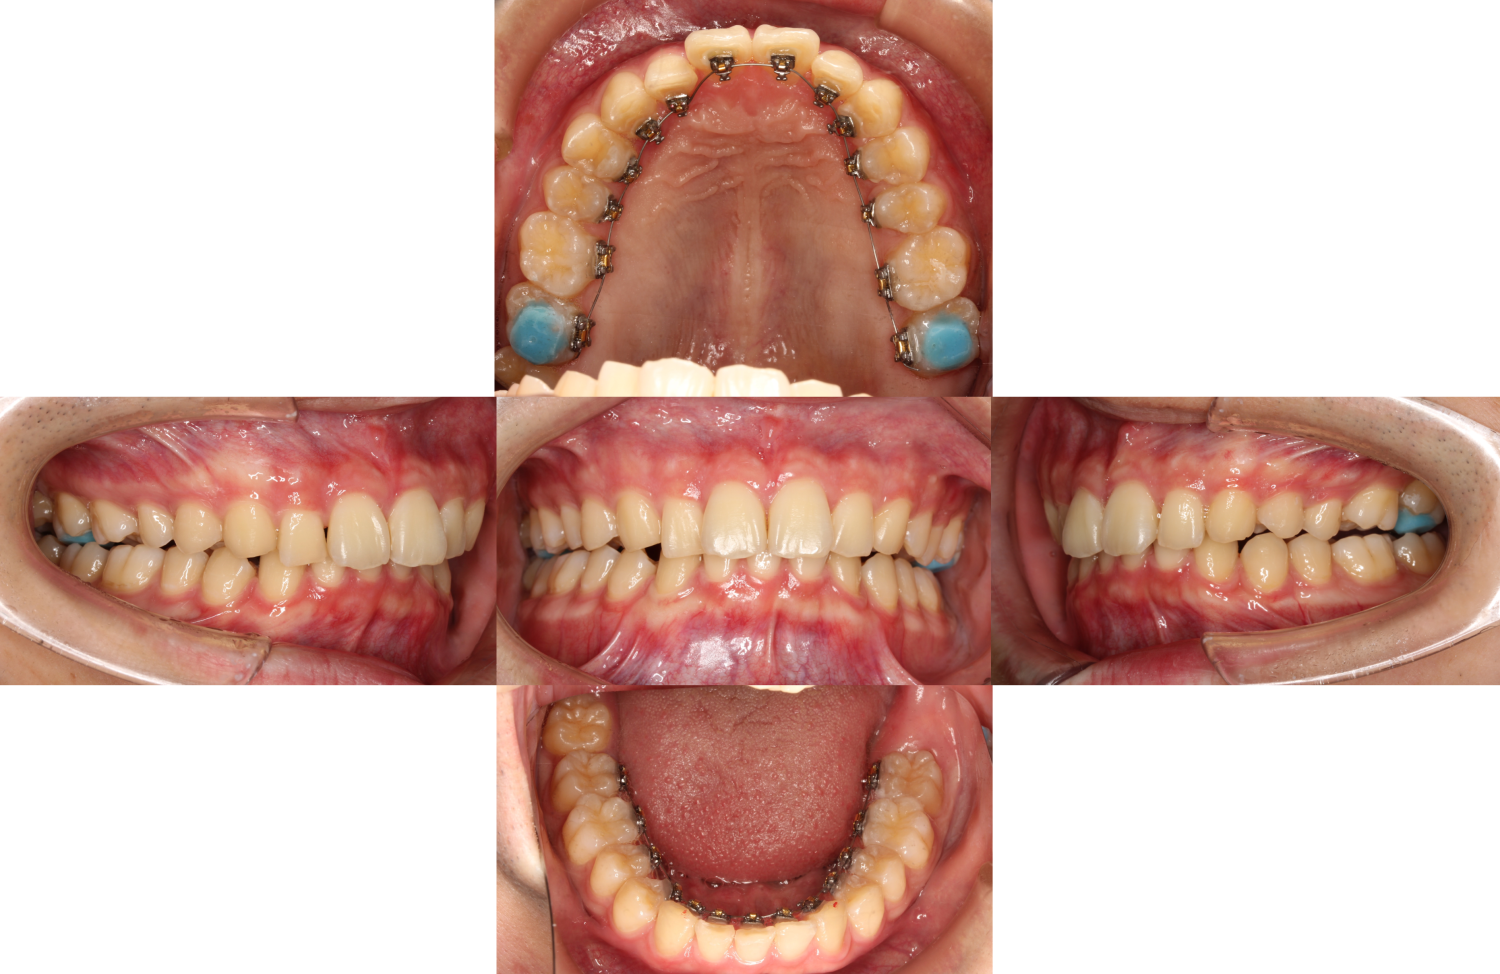

上下装置装着

過蓋咬合・裏側矯正の症例

上下の歯に装置を装着しました。

上の奥歯には「バイトアップ」と呼ばれる青色のレジンが付いています。

バイトアップは、嚙み合わせの調整や装置の脱離防止のために一時的に装着します。